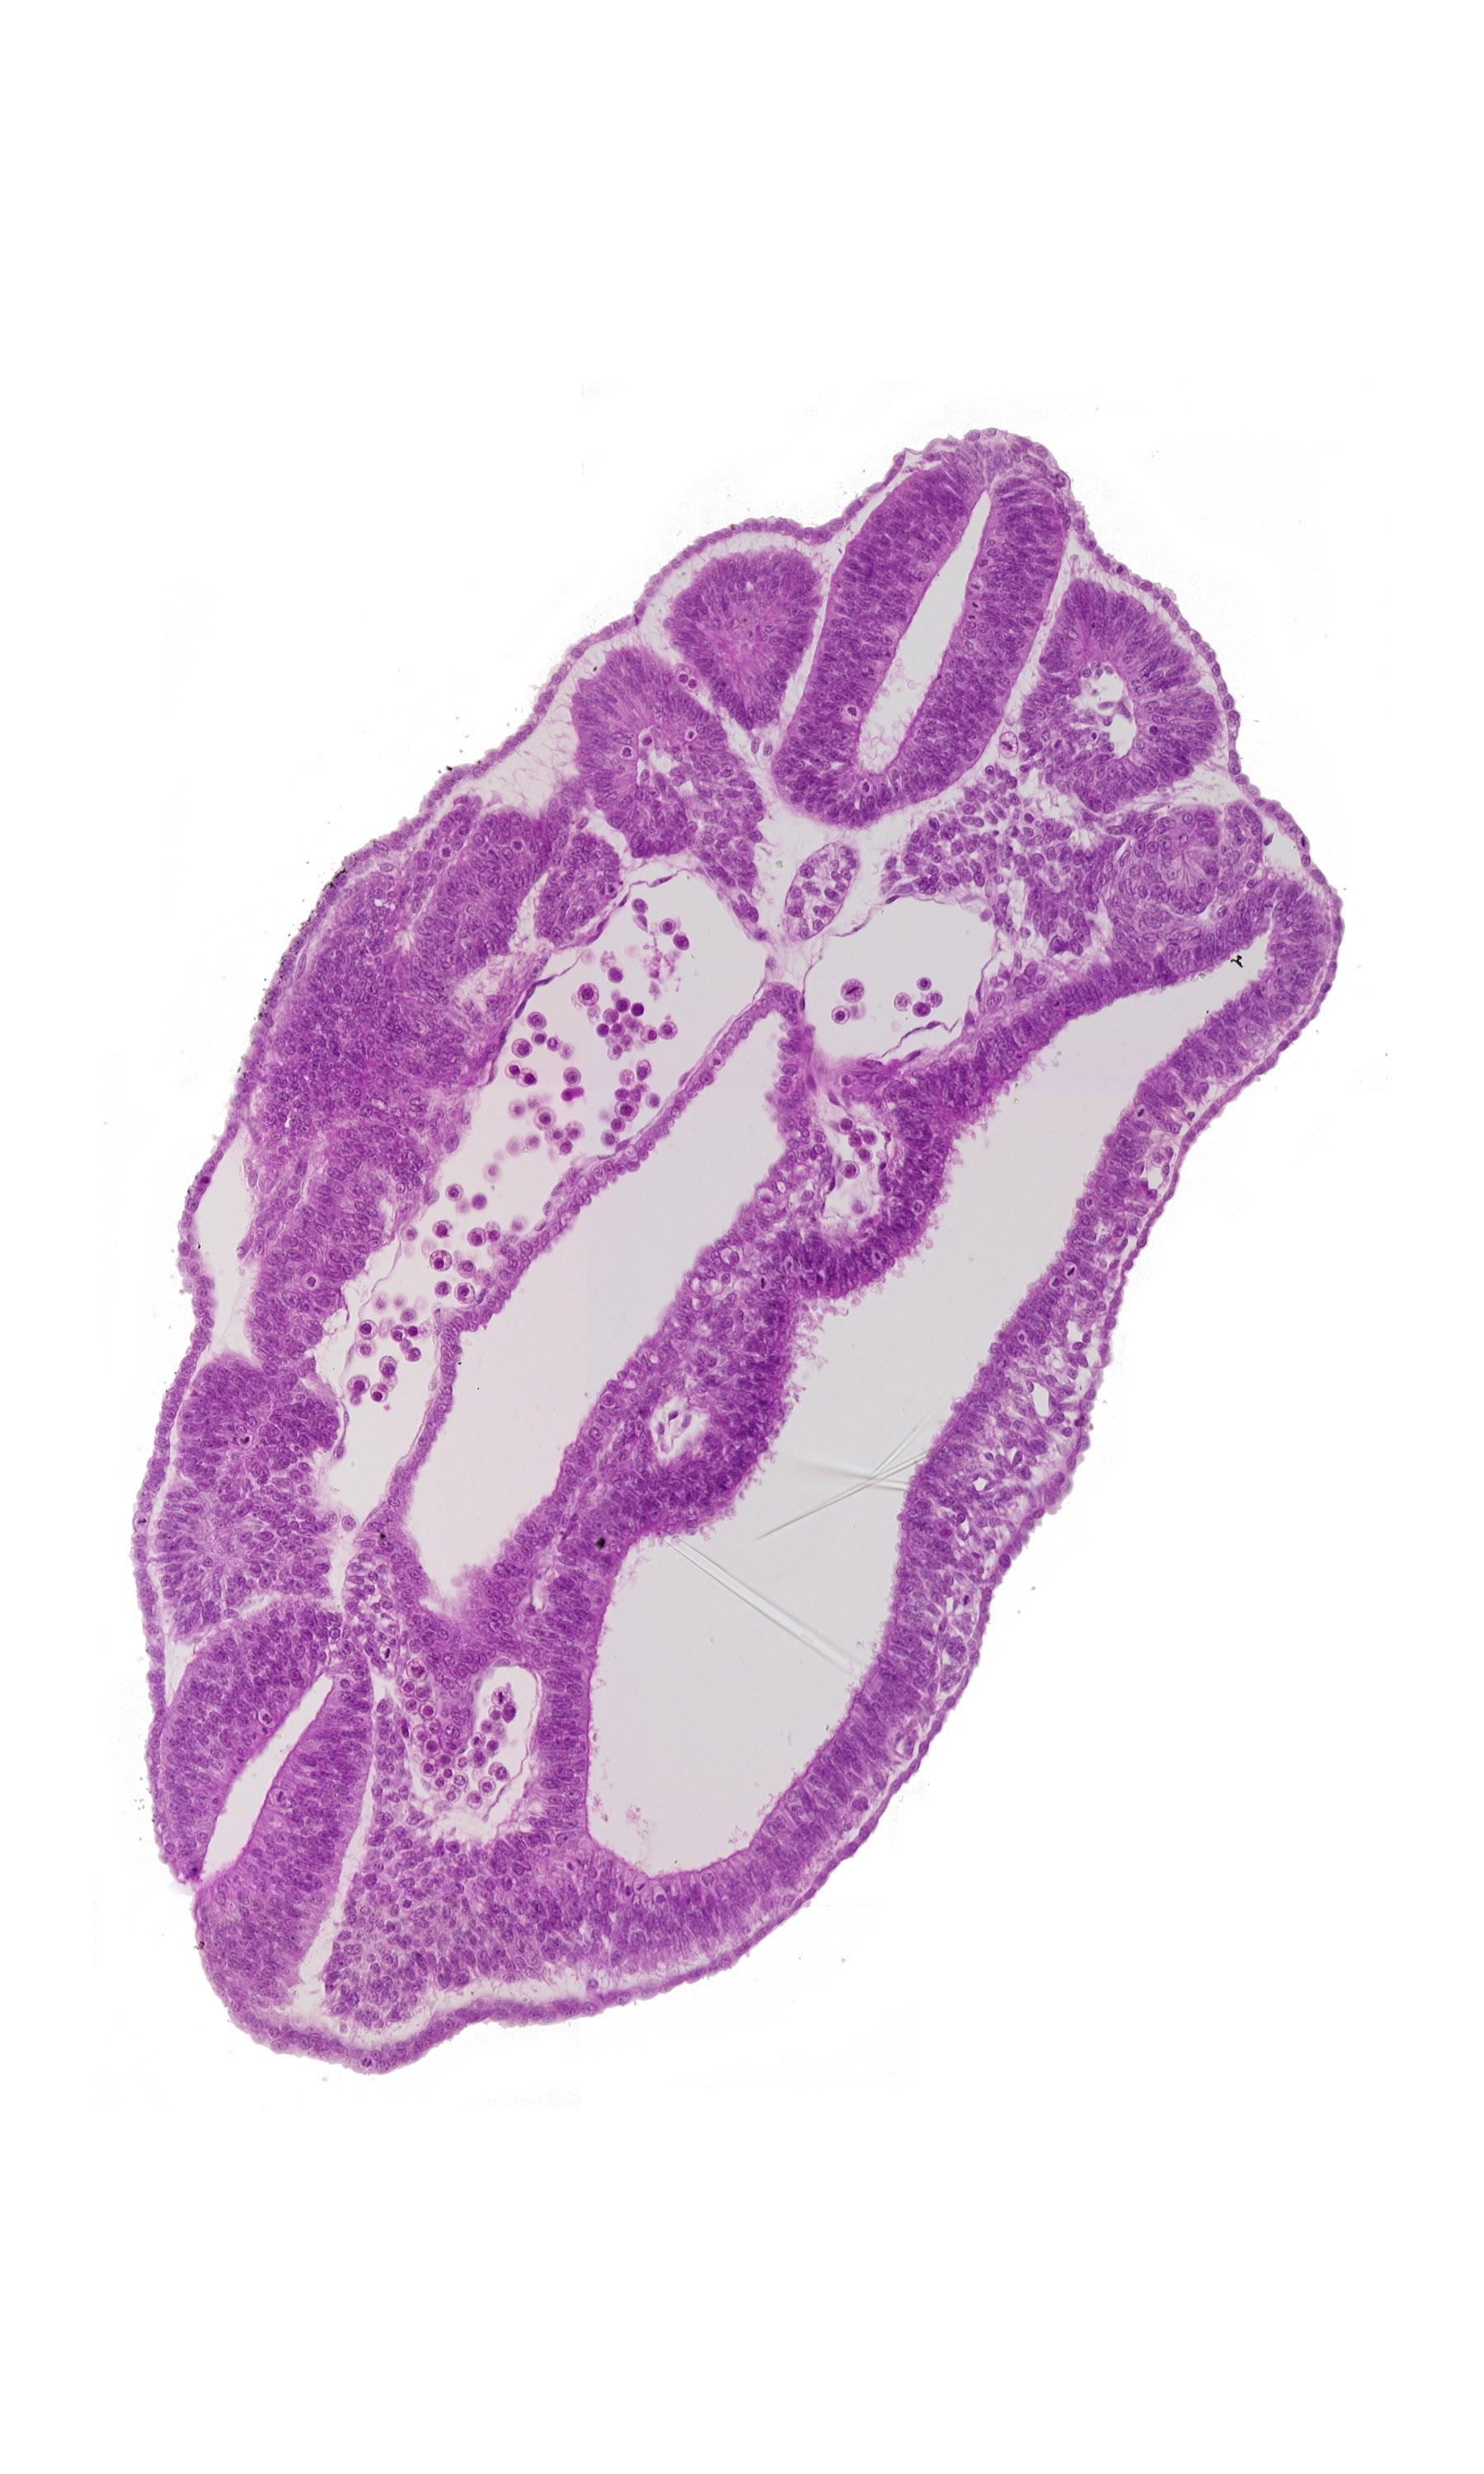

Carnegie Embryo #8943 | Location: 08-03-10

Keywords: dermatomyotome 16 (T-4), fusing neural folds, hindgut, junction of aorta and right common iliac artery, left common iliac artery, neural tube, notochord, perinotochordal lamina, peritoneal cavity, somatopleure, splanchnopleure, ventral edge of somite 17 (T-5)

Source: The Virtual Human Embryo.